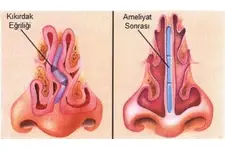

Kıkırdak Doku Çeşitleri Kıkırdak doku, bağ dokuları arasında yer alan, esnek ve dayanıklı bir yapıya sahip olan dokulardır. Farklı türleri ve işlevleri, vücudun çeşitli bölgelerinde önemli roller üstlenmektedir. Bu makalede, kıkırdak dokunun çeşitleri ve özellikleri detaylı bir şekilde ele alınacaktır. Kıkırdak Doku Türleri Kıkırdak doku üç ana türde sınıflandırılmaktadır: hyalin kıkırdak, elastik kıkırdak ve fibröz kıkırdak. Her bir tür, farklı yapısal özelliklere ve işlevsel amaçlara sahiptir.

Kıkırdak dokusunun hasar görmesi durumunda uygulanabilecek çeşitli tedavi yöntemleri bulunmaktadır. Bu tedaviler arasında fizik tedavi, ilaç tedavisi (ağrı kesiciler ve anti-inflamatuar ilaçlar), enjeksiyonlar (kortikosteroid veya hyaluronik asit) ve ileri vakalarda cerrahi müdahaleler yer alabilir. Cerrahi tedaviler arasında artroskopi, mikrokırık cerrahisi ve kıkırdak nakli gibi yöntemler bulunur.